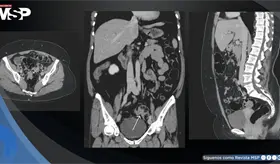

La paciente presentó cambios en el hábito intestinal y sangrado rectal con imágenes compatibles con lesiones estenosantes, inicialmente sospechosas de neoplasia sincrónica.

La trombosis de la vena espermática está asociada a enfermedades inflamatorias intestinales, como la colitis ulcerativa y la ileítis terminal, que generan un estado protrombótico debido a su naturaleza inflamatoria.